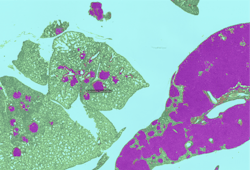

Carcinogenicity toxicology studies are one of the most complicated testing paradigms used in the safety assessment industry. Tissue evaluation involves upwards of 50,000 slides per study by the toxicologic pathologist. The primary purpose of these studies is to characterize any proliferative changes that may indicate that the test agent increases the risk for cancer in humans or animals. Sensitivity and specificity are important in these studies as is the toxicologic pathologist’s assessment of the relevance of any finding to human or animal health.10 AI-CNNs at CRL were recently developed to identify proliferative changes in the lung in a common model system used for carcinogenicity. (Figure 2)

Figure 2: AI-CNN prediction (Deciphex Patholytix AI) of lung adenomas in urethane-treated TgRasH2 mice

The toxicologic pathologist trained the AI-CNN to recognize two different important classes of proliferative lesions expected with the treatment administered. After training, the AI-CNN algorithm identified lesion hot spots in a test set at 100 percent concordance with a group of six toxicologic pathologists.11 This screening approach promises to accelerate the workflow for the toxicologic pathologist in carcinogenicity studies and is being investigated in additional tissue types. The AI-CNN could prepare a visual data set that is delivered to the pathologist with the study slides. The pathologist would use the screening data to support an efficient and targeted approach to analysis and provide study sponsors with an earlier indication of potential toxicity. We expect the AI-CNN will also accelerate the entire slide review process. As the pathologist identifies novel lesion patterns in the tissues, additional training could be provided to the AI-CNN to increase the breadth of the algorithm’s ability to not only identify the abnormal but also suggest standardized diagnostic terminology and when appropriate a severity grade.